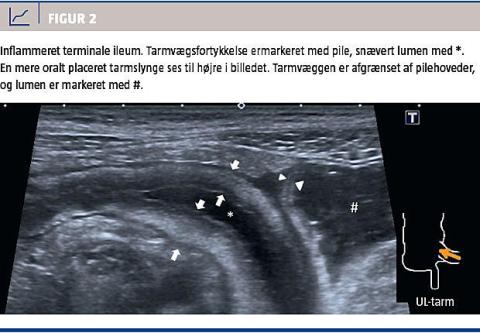

Mb. Crohn og colitis ulcerosa medfører tarmvægsfortykkelse, som ofte ses tydeligt ved UL. Udbredelsen af colitis ulcerosa sker fra rectum og kontinuert i oral retning. Afgrænsningen oralt kan nemt afgøres, når udbredelsen strækker sig op i sigmoideum. Mb. Crohn er en transmural kronisk tarminflammation med 69-77% involvering af terminale ileum [25]. Da terminale ileum ofte er let at identificere, er UL et effektivt redskab. Hyppigt ses der vægfortykkelse ≥ 5 mm, og længden kan forsøges estimeret, hvilket er mest præcist for korte segmenter (Figur 2) [4, 11]. Peristaltikken er betydeligt nedsat i det afficerede segment. En metaanalyse har vist, at den diagnostiske sensitivitet og specificitet for Crohnforandringer i terminale ileum er hhv. 88% og 93%, når afskæringsværdien for vægfortykkelse er 3 mm, 75% samt 97% ved en afskæringsværdi på 4 mm [26]. Der foreslås derfor, at > 4 mm bruges som nedre grænse ved primærdiagnose, og > 3 mm kan være et tegn på aktiv sygdom ved followup ved kendt mb. Crohn [26]. Stenoser kan identificeres som vægfortykkelse, indsnævret lumen, præstenotisk dilatation og atypisk

hyperperistaltik eller subileus. Mb. Crohn kan også medføre ekstraintestinale patologiske forandringer såsom inflammeret mesenterium, der ses som en hyperekkoisk nonkompressibel masse, forstørrede mesenterielle lymfeknuder, hypervaskularitet, ascites samt fistler og abscesser ved komplikationer [4, 11].